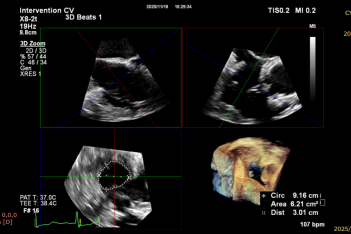

Ultrasound Evaluation: Severe tricuspid insufficiency (mean vena contracta 9mm), with the regurgitation orifice located at the anteroseptal commissure. The mechanism of regurgitation is myxomatous degeneration of the valve leaflets, accompanied by poor leaflet coaptation or reduced coaptation height. The mean diameter of the tricuspid annulus is 37mm. Echocardiographic evaluation confirmed that the anatomical structure is suitable for the K-Clip® system.

Implanting the second clip at the anteroposterior commissure following the same procedure

After implanting one 12T K-Clip® device at the commissure of the posterior and septal leaflets of the tricuspid valve and another 12T K-Clip® device at the commissure of the posterior and anterior leaflets, the overall area of the tricuspid annulus was reduced. Tricuspid regurgitation was decreased from severe (4+) preoperatively to moderate (2+), the regurgitation was effectively alleviated, the surgical effect met the expected goals, and the surgery was successfully completed.